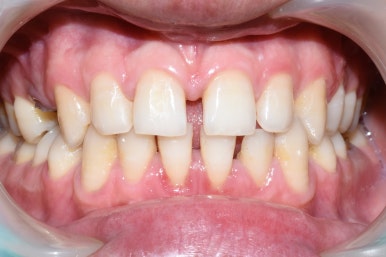

스케일링 전 , 후/ 시청역 연세예감치과

스케일링 전 후

이렇게 스케일링을 하고 나면 치석이 없어지면서 치아가 빈것처럼 느껴질 수도 있고

부어있던 잇몸부분은 피가 나기도 하는데요

빈 부분이 생길지라도 없어야 하는 쓰레기(?)는 처리해야 하는 거니 스케일링은 해야겠죠.

또한 치아를 덮고있던 치석이 없어지면서 시린 느낌이 있을 수도 있으나, 없애야 하는 치석은 없애야합니다[! 단호]